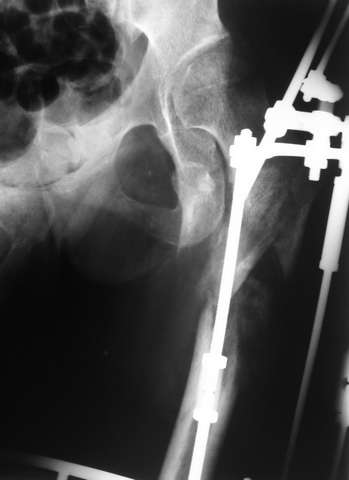

Девушка 21 года 02.10.07 г. пострадала в результате падения с высоты 4-го этажа при пожаре в одном из студенческих общежитий г. Москвы. Получила тяжелую сочетанную травму, в том числе закрытый оскольчатый чрез- и подвертельный перелом левой бедренной кости. Лечилась в одной из больниц столицы. Бедро было фиксировано при помощи скелетного вытяжения. Через полтора месяца после травмы переведена в институт им. Склифосовского. У больной имелись: поддиафрагмальный абсцесс, трахеопищеводный свищ, трахеостома, гастростома, несостоятельность швов раны передней брюшной стенки, укорочение левого бедра на 10 см (рентгенограммы при поступлении - рис 1.). В середине декабря был наложен спицестержневой аппарат, с помощью которого к сегодняшнему удалось устранить укорочение бедра (рис. 2). В течение последних 4-х дней устраняем смещение дистального отломка бедренной кости по ширине. Раны на передней брюшной стенке почти зажили. Температура тела и лабораторные показатели нормальные. Планируем выполнить закрытый остеосинтез левой бедренной кости удлиненным проксимальным бедренным штифтом производства фирмы "Остеомед". Нас смущает, что малый вертел бедренной кости остается значительно смещенным проксимально и кнутри.